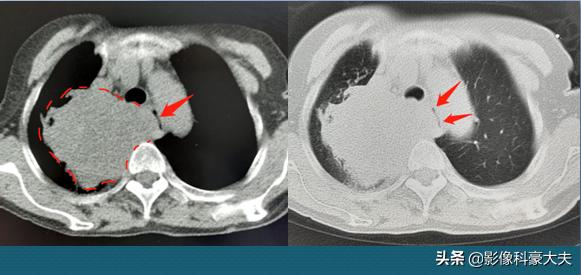

这是一位76岁老人,吞咽困难2个月,越来越严重,这5天只能喝点稀饭牛奶了,担心是食管癌,结果听诊右肺呼吸音很低,医生建议做肺部CT看看。

右侧肺癌,9.2cm的大肿块,把食管挤扁到一边,只剩下一条很窄的缝隙(红色箭头所指就是食管),饭团都咽不下去了……

很遗憾,老人之前没有明显咳嗽症状,只是偶尔有一点胸闷,很多老人勤劳朴实,善于忍耐,结果就拖太久了……

这个已经无法手术,只能采用一些方法让肿瘤缩小,改善症状,解决吃饭问题,长期疗效恐怕不乐观。